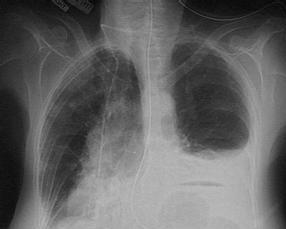

组织细胞增生症为一组少见的原因不明疾病,该病名由Lichtenstein于1953年提出。该病多发生于儿童,其发病、临床症状及病变范围差异很大,但病理上有着共同的病理特征,即组织细胞异常增生。现已证实此组织细胞具有朗格汉斯组织细胞(langerhans’ histocyte)特征,故本病现又称为朗格汉斯组织细胞增生症。